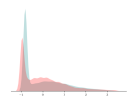

We adopt commonly-used statistical metrics, F1-score, recall and precision, to quantitatively evaluate classification performance. , and F1-score is the the harmonic mean of precision and recall. We report the average scores of these metrics for all examined methods. As suggested by [4], we utilize the -distance as a measure of domain divergence to quantitatively evaluate the separation of categorical and domain features. Similar to [19, 53], we train a SVM as a domain classifier to compute (the error of classifier) for the -distance, .

We compare the -distance of categorical features and domain features. Fig. 5 (a) shows that domain difference is higher in domain features than in categorical features. This indicates that domain features contain more domain information whereas categorical features are more domain-invariant. Fig. 6 shows the t-SNE plot of categorical features in both domains for MIDNet. From Fig. 6 (a), we observe that the categorical features learned by MIDNet enable the anatomical classification. Fig. 6 (b) shows that the learned categorical features are domain-invariant.

The classification performance of baselines and the proposed model are shown in Table. III. We observe that MIDNet outperforms the state-of-the-art on on the most important test data for average F1-score and recall. Among all the models in the ablation study, MIDNet+ achieves the best performance on and , demonstrating that metric learning contributes to the separation of seen categories in both domains. MIDNet outperforms MIDNet w/o , MIDNet w/o and MIDNet w/o on , illustrating the importance of all proposed components in MIDNet for the classification of unseen categories in the target domain. In addition, Fig. 7 (b) shows the effectiveness of mutual information disentanglement () to learn domain-invariant categorical features.